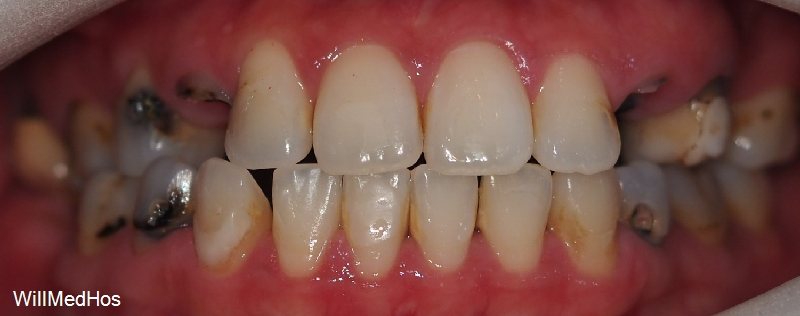

위의 사진이 최종 치료 사진 입니다. 뼈이식, 신경치료 후 크라운, 임플란트 치료를 진행 하였고

최종 기간은 10개월 정도 소요 되었습니다.

▲ 최종 완료 구강 사진